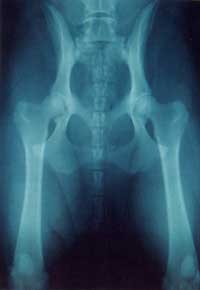

The only way to assess properly the presence or relative absence

of HD is by radiography. This is an accurate photographic way

of showing the position ofthe ball of the joint in relation

to the socket and the presence and degree of any secondary changes. |